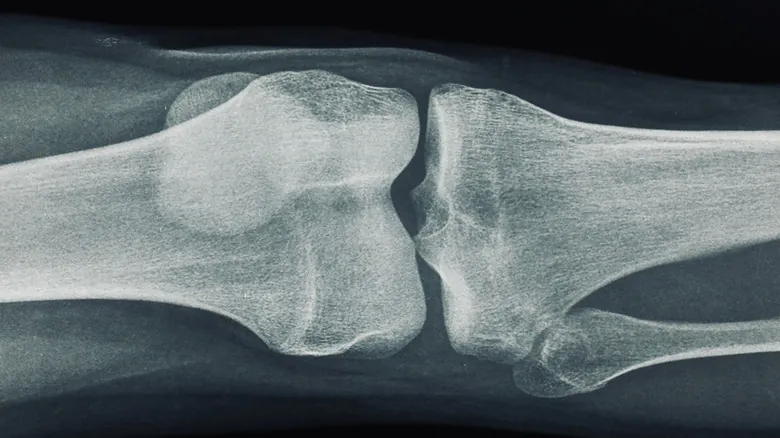

El curioso nombre de “hueso de la risa” es, apropiadamente, un juego de palabras. Se origina porque el nervio cubital pasa justo al lado del húmero en el codo, el hueso de tu brazo superior. “Húmero” suena muy parecido a “humoroso”, y de ahí la asociación con la sensación repentina y “graciosa” que se siente. El húmero es, después de los huesos de las piernas, el hueso más largo del cuerpo humano. En su extremo, cerca del codo, se encuentra una protuberancia ósea en el lado interno, que puedes sentir al tocarte la parte interior del codo, llamada epicóndilo medial. Es precisamente esta estructura la que sirve de punto de impacto cuando golpeamos el codo.

Cuando tu codo choca contra algo, el nervio cubital se comprime bruscamente contra el epicóndilo medial del húmero. Esta colisión provoca una sensación de dolor agudo que irradia por todo el brazo hasta la mano, acompañada a menudo de hormigueo o una especie de “shock” eléctrico. Aunque la sensación es intensa y muy molesta, generalmente no hay de qué preocuparse. En la mayoría de los casos, el dolor desaparece en cuestión de segundos. Sin embargo, existen situaciones donde el daño al nervio cubital puede ser mucho más serio y requerir atención.

El síndrome del túnel cubital es una de las afecciones nerviosas más comunes. La compresión constante del nervio cubital puede afectar la conductividad de las células nerviosas, lo que ralentiza las señales que van desde el cerebro hasta las manos. Con el tiempo, esto puede llegar a destruir las fibras nerviosas, provocando entumecimiento, debilidad muscular en la mano y, en casos avanzados, incluso la pérdida de destreza en los dedos afectados. Los factores de riesgo para desarrollar el síndrome del túnel cubital incluyen fracturas óseas previas, dislocaciones y condiciones como la artritis en la articulación del codo.